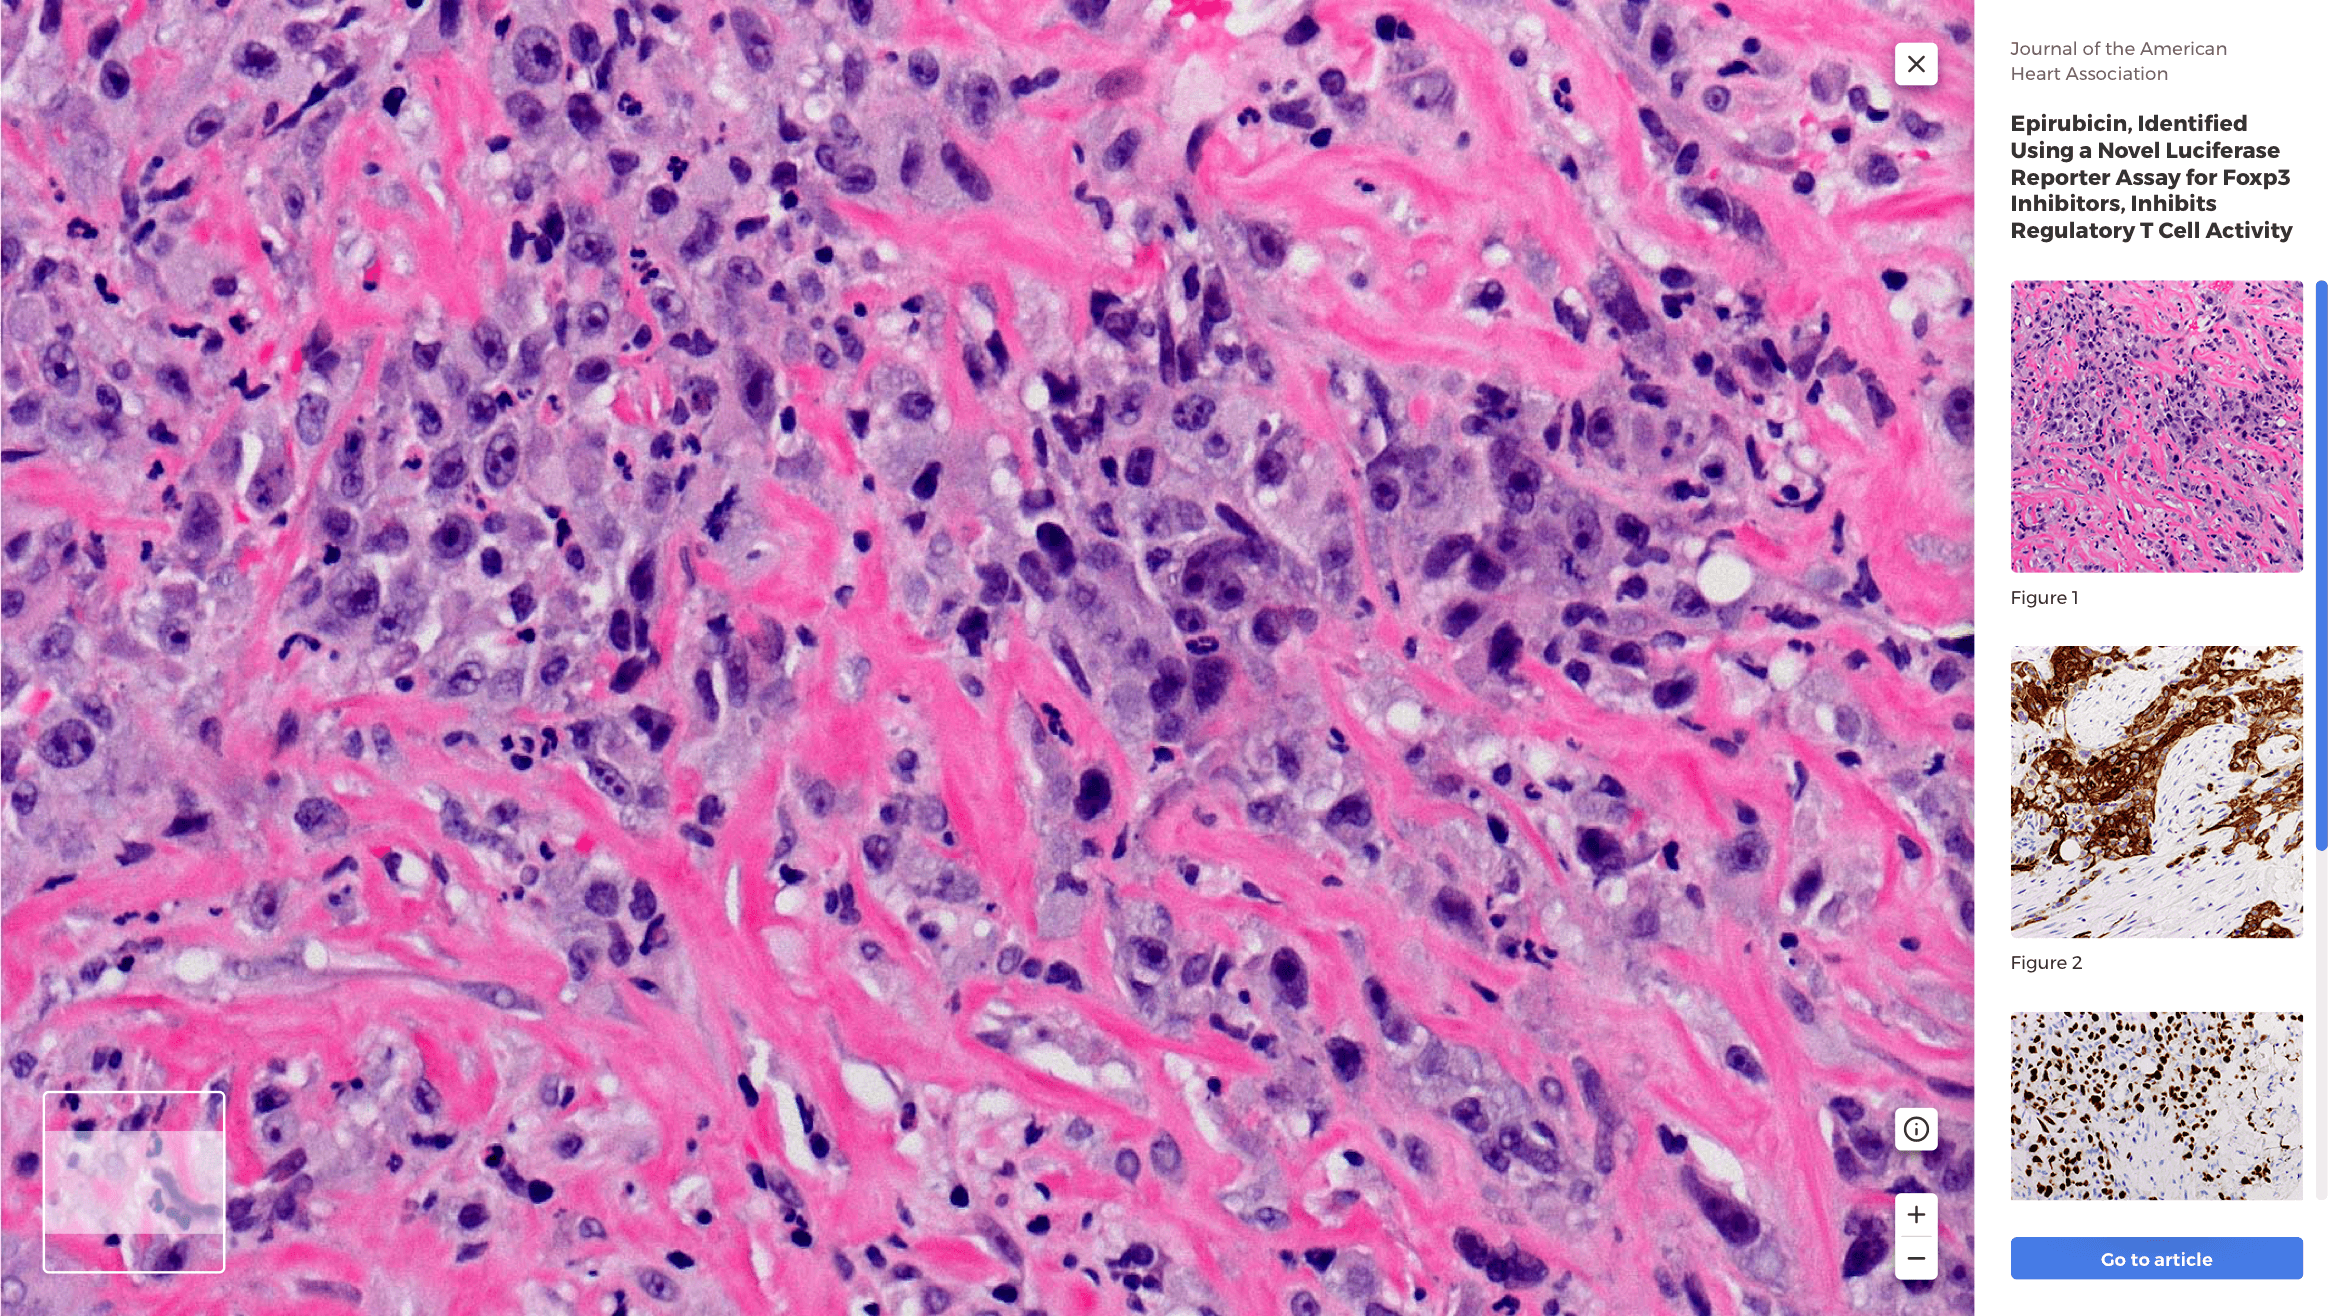

In addition to their search tool, shown below, Bioz syndicates their score through vendor catalogs, and publishing journals alike.